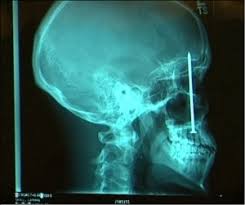

3. Kesehatan

Pada bidang kesehatan Grafik Komputer digunakan untuk meRontgen bagian tubuh manusia, untuk mengetahui ada atau tidaknya kelainan dalam tubuh.

1. Bidang Kedokteran